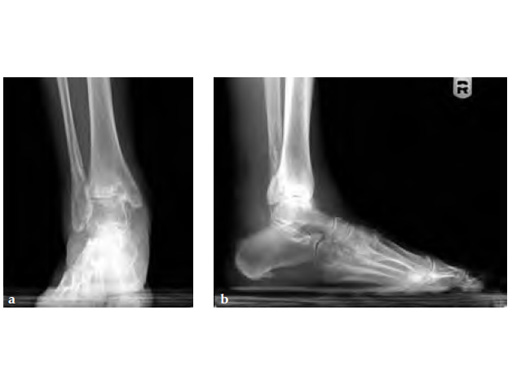

58-year-old male

Case provided by Andrew Sands, New York, USA

Previous plafond fracture and ORIF through large anterior incision. Increasing pain not relieved by nonoperative preoperative workup revealing deep bony infection. The interim procedure was deep biopsy, curettage and placement of antibiotic self-dissolving beads. Generation IV antibiotics were given. The reimaging showed infection had gone.